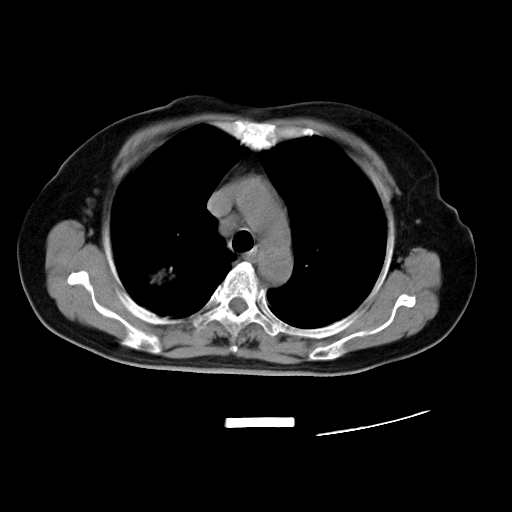

以下是引用zjzjr在2007-3-23 13:28:00的发言:[br]右肺上叶后段可见一结节状高密度影,可见毛刺征,胸膜凹陷征及血管导入征,纵隔内可见肿大淋巴结影.考虑右肺上叶周围型肺癌伴纵隔淋巴结转移.

以下是引用zjzjr在2007-3-23 13:28:00的发言:[br]右肺上叶后段可见一结节状高密度影,可见毛刺征,胸膜凹陷征及血管导入征,气管前腔静脉后可见肿大淋巴结影.考虑右肺上叶周围型肺癌伴纵隔淋巴结转移.